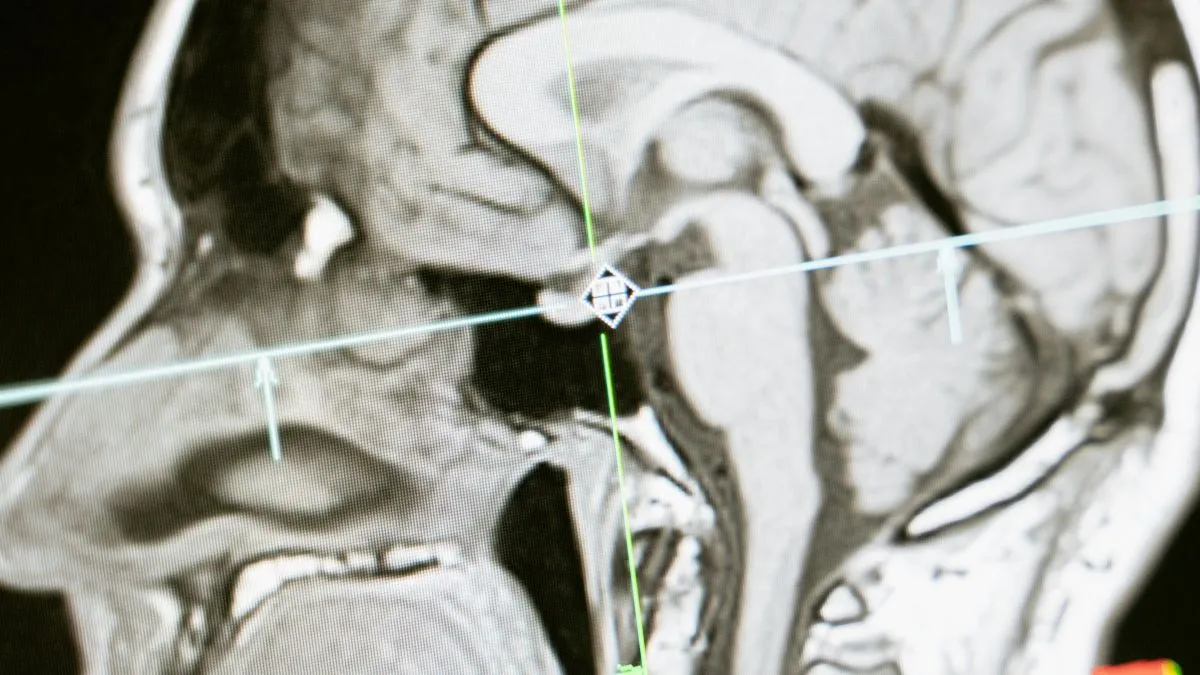

Mi az Alzheimer-kór?

Az Alzheimer-kór a gondolkodás és a megismerési funkciók beszűkülésével, magatartásváltozással, elbutulással (demencia), majd gyors biológiai leépüléssel járó neurodegeneratív betegség. Előfordulása az életkor előrehaladtával növekszik, a 65 év felettiek kb. 5%-át, a 80 év felettiek kb. 20%-át érinti, Magyarországon 200 000 ember szenved ebben a betegségben. Az Alzheimer-kór pontos kiváltó oka lényegében ismeretlen, ugyanakkor a genetikai hajlamnak jelentős szerepet tulajdonítanak, valamint a környezeti hatások és az életmód is beleszól a betegség kialakulásába.